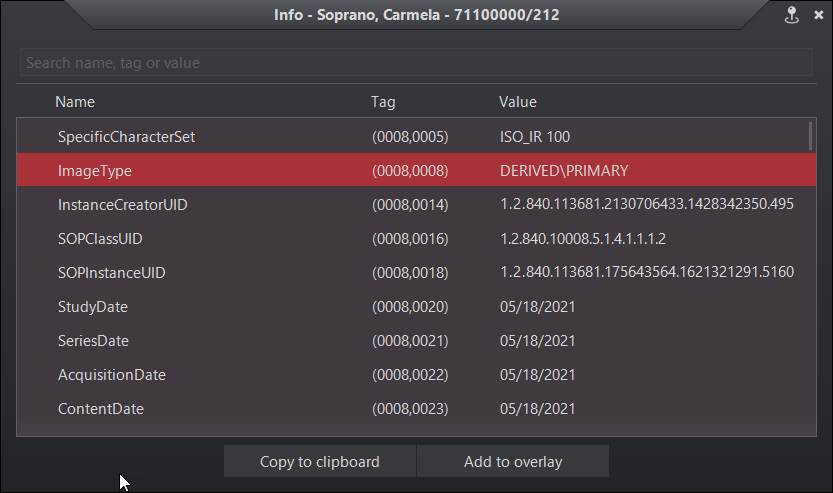

A DICOM információs panel frissült, hogy megfeleljen az Evo nézegető megjelenésének és hangulatának. A panel tartalmaz keresési funkciókat, vágólapra másolást és overlay hozzáadása opciót.